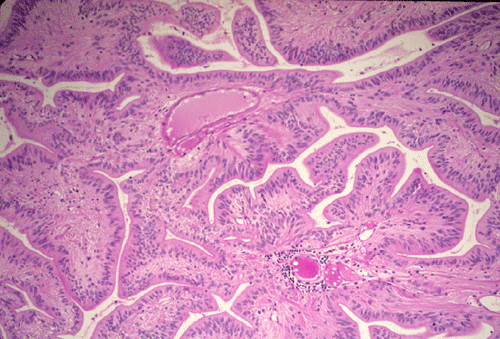

The histopathology of the tumor is fairly similar in different parts of the of the tumor and the papillary structures are the obvious (Panel A). On medium and high magnification (Panel B and C respectively), the cores of the papillary structure is composed of thin walled blood vessels. The tumor cells appear to appear in a pattern reminiscent of the pseudocolumnar arrangement of the respiratory respiratory epithelium except that no basement membrane can be identified. The cores are also not composed of collagenous tissue but by fibrillary process that appear to extends from the nuclei. A zone of hyponuclear area is present between the nuclei and the vascular channels (delimited by arrows in Panel C). No cilia are noted on the surface epithelium and no mucin production is noted. The cytoplasmic border is very indistinct. The nuclei appear to be rather bland appearing and mitotic figures are not readily seen. There is neither endothelial proliferation nor necrosis.

The diagnostic pattern of ependymoma is best visualized with very low magnification under the microscope [Click here to see pictures of classic ependymomas]. Ependymomas are characterized by a perivascualr radial formation of isomorphic tumor cells with a nuclear-free zone that form a cuff around the vessels is an important diagnostic feature. The tumor cells have fibrillary cytoplasmic processes that taper into this cuff. Ependymal canals are tubular structures lined by ependymal cells. A basement membrane is characteristic missing and the cells with distinct epithelial morphology merges distinctly with the underlying tumor cells. Although they are not common features but is of great diagnostic value when being found. Mitotic figures, if present, should only be sporadically seen. Cystic component and calcifications may be present.  Significant pleomorphism, increased mitotic activities, and necrosis are suggestive of anaplastic ependymoma (WHO grade III).

Papillary ependymoma, as illustrated in this case, is a rare variant. These tumors typically appear as papillary fronds covered by multilayered ependymal tumor cells. The most superficial layer may have epithelium-like surfaces similar to those of ependymal rosettes. These tumors must be distinguished from metastatic papillary carcinomas and choroids plexus tumors. One salient feature is that papillary ependymomas have no basement membrane. The superficial epithelial tumor cells merge imperceptibly with the underneath tumor cells. Papillary ependymoma can express cytokeratin. It is not rare to see focal papillary formation in an otherwise classic ependymoma. However, tumors composed predominantly of papillary structure as illustrated in this case is uncommon.